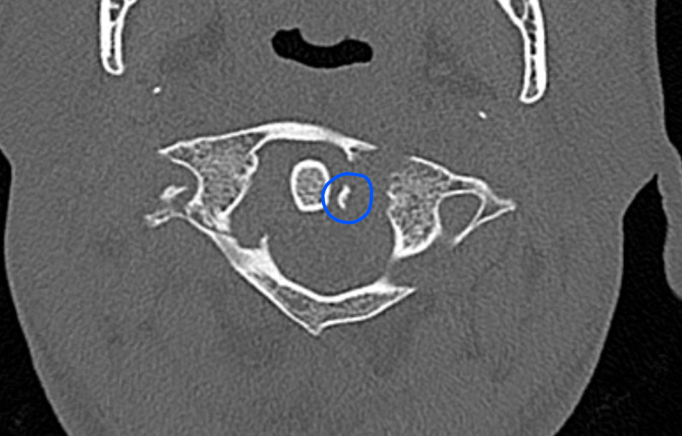

CT

Better defines displacement, ADI, LMD and bony avulsions of the transverse ligament

Avulsionlig avulsion

CT axial slices "Jefferson" (burst) fracture with bony avulsion (blue) of the transverse ligament